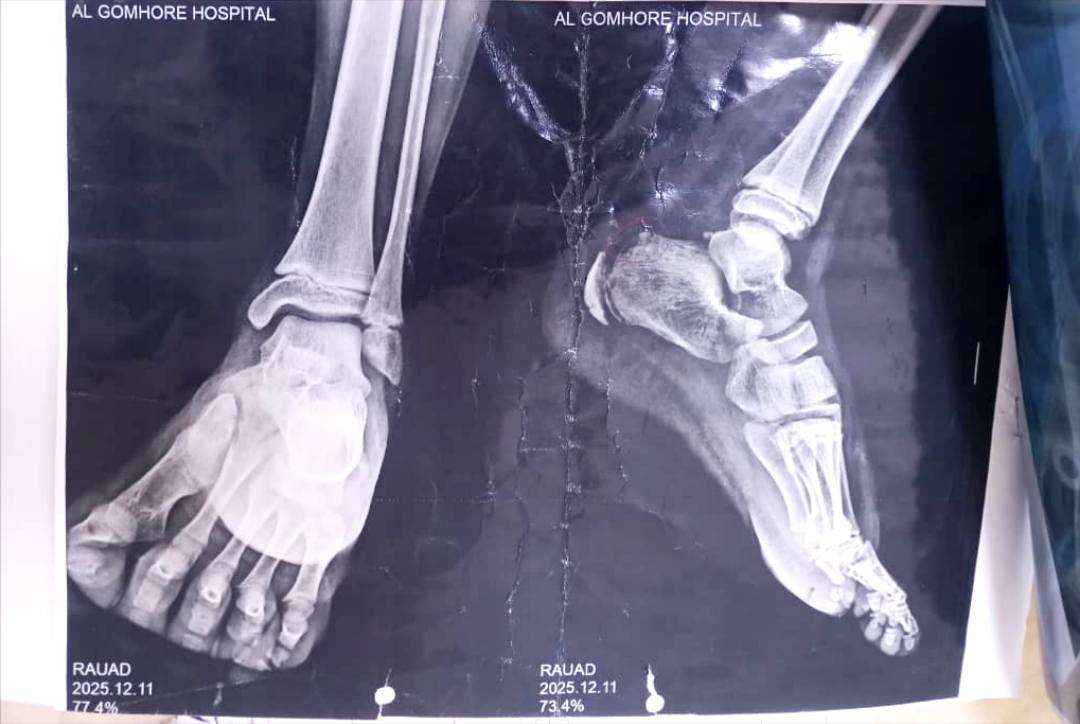

تعرّض الطفل رياض، البالغ من العمر 12 عامًا، لحادث مؤلم بعد أن كان يركب دراجة (سيكل)، حيث علِقت قدمه في السلسلة، ما أدى إلى إصابة خطيرة تسببت بكسر في عظم القدم مع انقطاع الوتر، بحسب إفادات طبية.

وأفادت مصادر محلية بأن الطفل نُقل على وجه السرعة إلى مستشفى الجمهورية، حيث أوضح الأطباء أن حالته تتطلب عملية جراحية أولية عاجلة لسحب الوتر وربطه، محذرين من أن أي تأخير قد يؤدي إلى مضاعفات دائمة وعدم عودة القدم إلى وضعها الطبيعي.